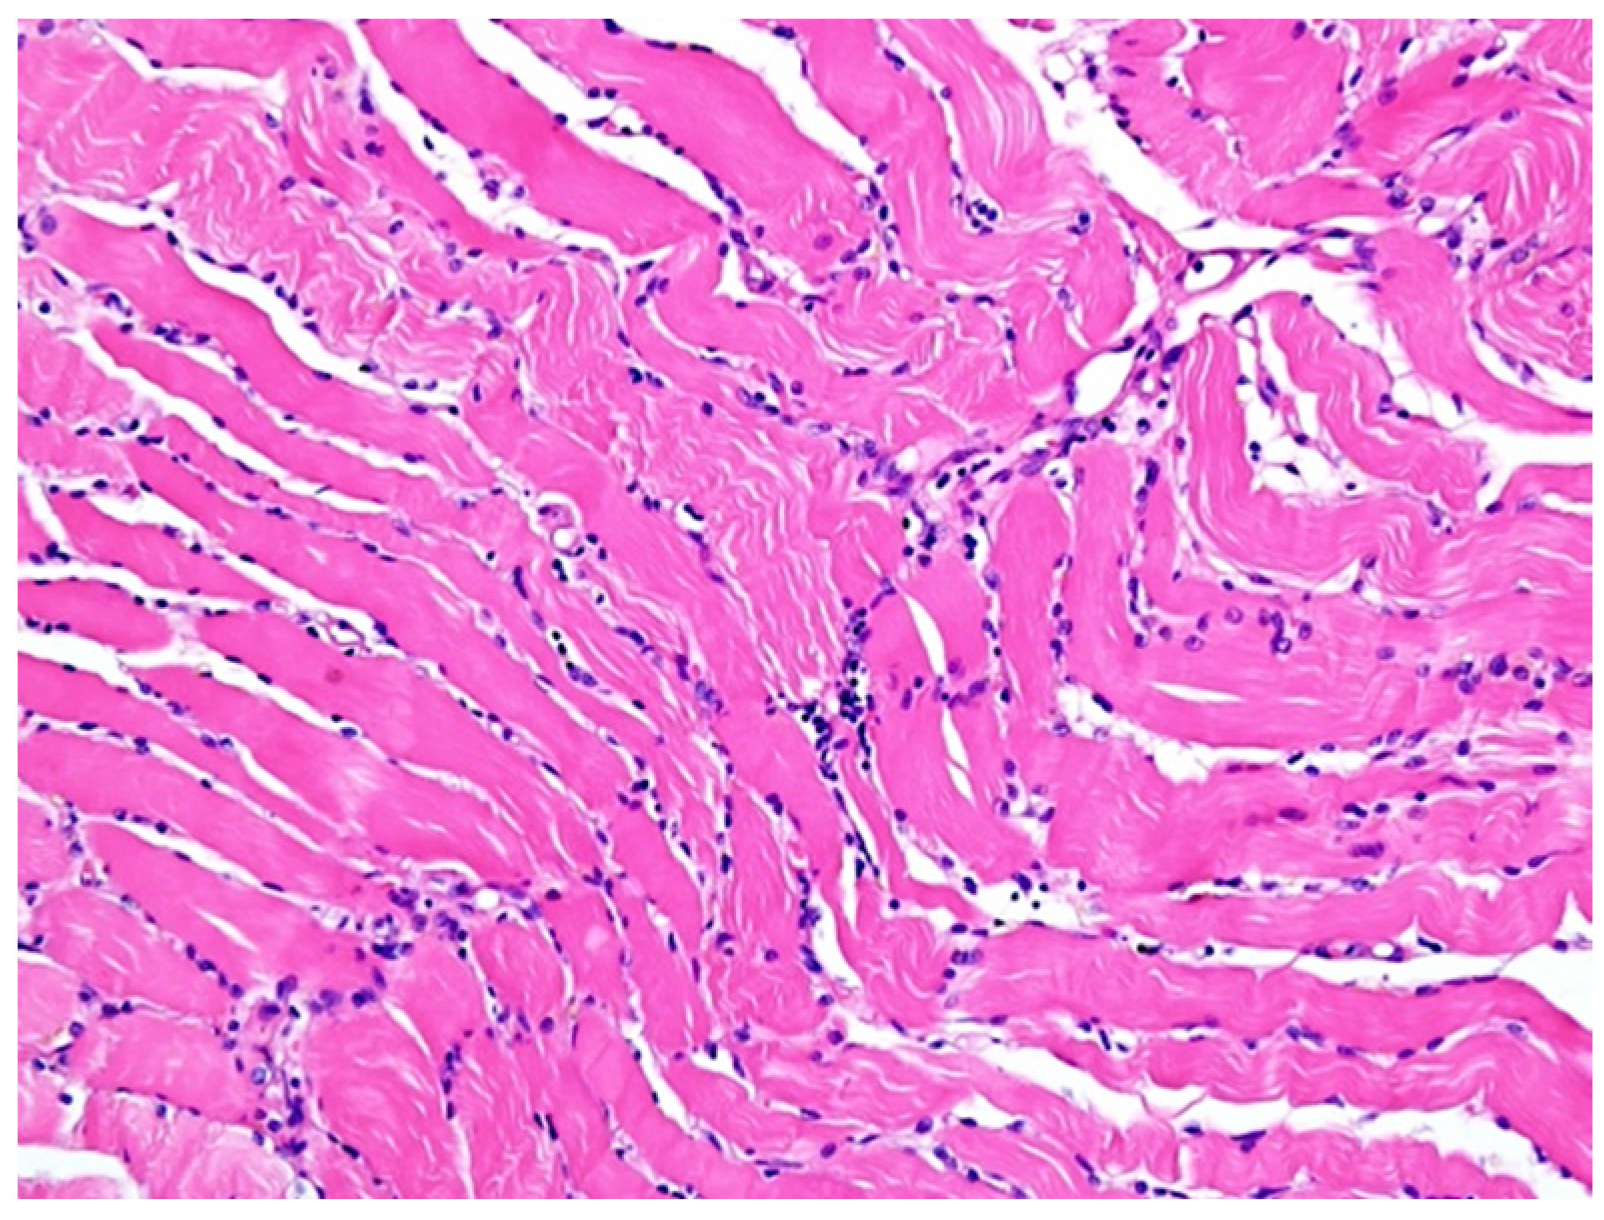

3. Results